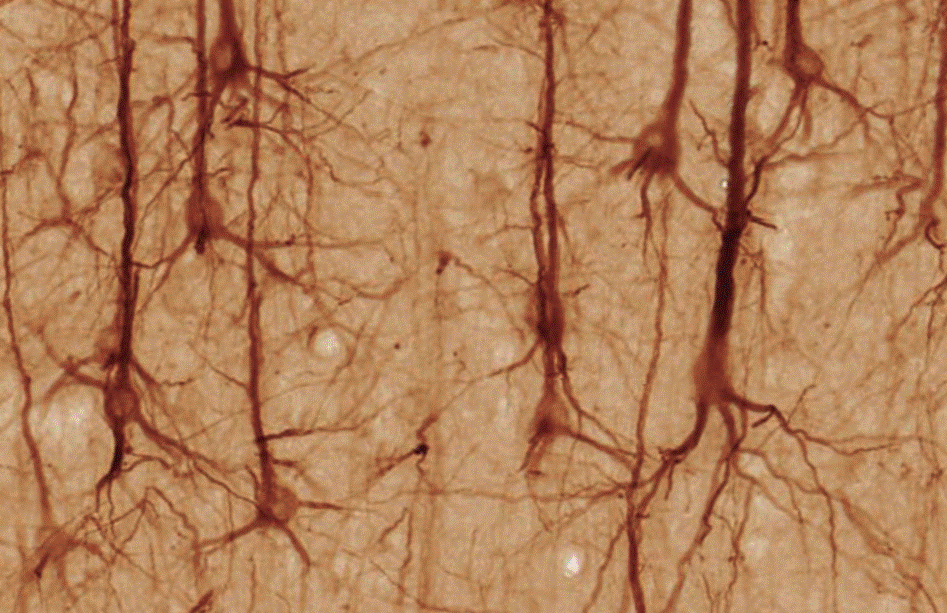

Las células del SNC se encuentran en un balance de señalización de factores inmunes y neurotróficos que están enfocados en mantener la homeostasis del tejido (Figura 1), principalmente estos estímulos tienen la finalidad de inhibir la respuesta inmune proinflamatoria de la microglia.

Figura 1 Estructura y organización del SNC y la BHE. En estado fisiológico tanto el astrocito como la neurona expresan marcadores (CD200, CD22, CD95L, CX3CL1) y secretan tanto factores inmunes (CD95L, CX3CL1, IL-10, TGFβ) como neurotroficos (NGF, BDNF, NT-3, GABA, dopamina, NE) con el fin de mantener en estado quiescente a la microglia, evitando su activación y el inicio de la cascada neuroinflamatoria.